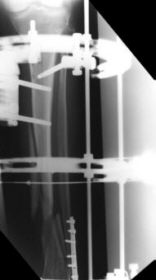

Case 1

A 42 year old lady sustained a severe comminuted fracture of her right tibia in a road traffic accident.

The fracture was treated with a 3 ring Sheffield Hybrid Fixator. 3 compressive olive wires were inserted across the diaphyseal fracture site using the middle ring and 2 wire slider units. The pilon fracture was reduced with olive wires. Union was uneventful.